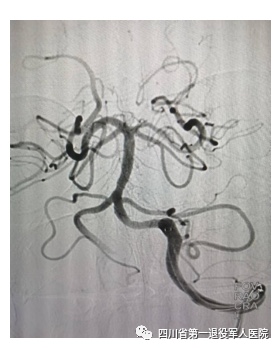

患者为37岁青年男性,因“吐词不清、右侧肢体无力7小时”入院。入院时神经专科查体:吐词不清,右侧鼻唇沟较对侧变浅,伸舌右偏,口角略向左侧歪斜。右侧上下肢肌力0级,右侧巴氏征阳性。NIHSS评分:10分。入院诊断为急性脑梗死。患者已过静脉溶栓时间窗,有急诊动脉取栓指征。神经内科立即联合相关科室团结协作,经上级医院指导,完善各项检查后在局麻下行全脑血管造影术+机械取栓术,术中见基底动脉中段血栓样物质,通过中间导管抽吸少许血栓,再次造影见基底动脉血流通畅,管壁光滑,未见明显血栓物质,远端血流mTICI 3a级。术后,患者临床症状明显改善,吐词清晰,右上肢肌力5-级,右下肢肌力4-级,NIHSS 评分:2分。